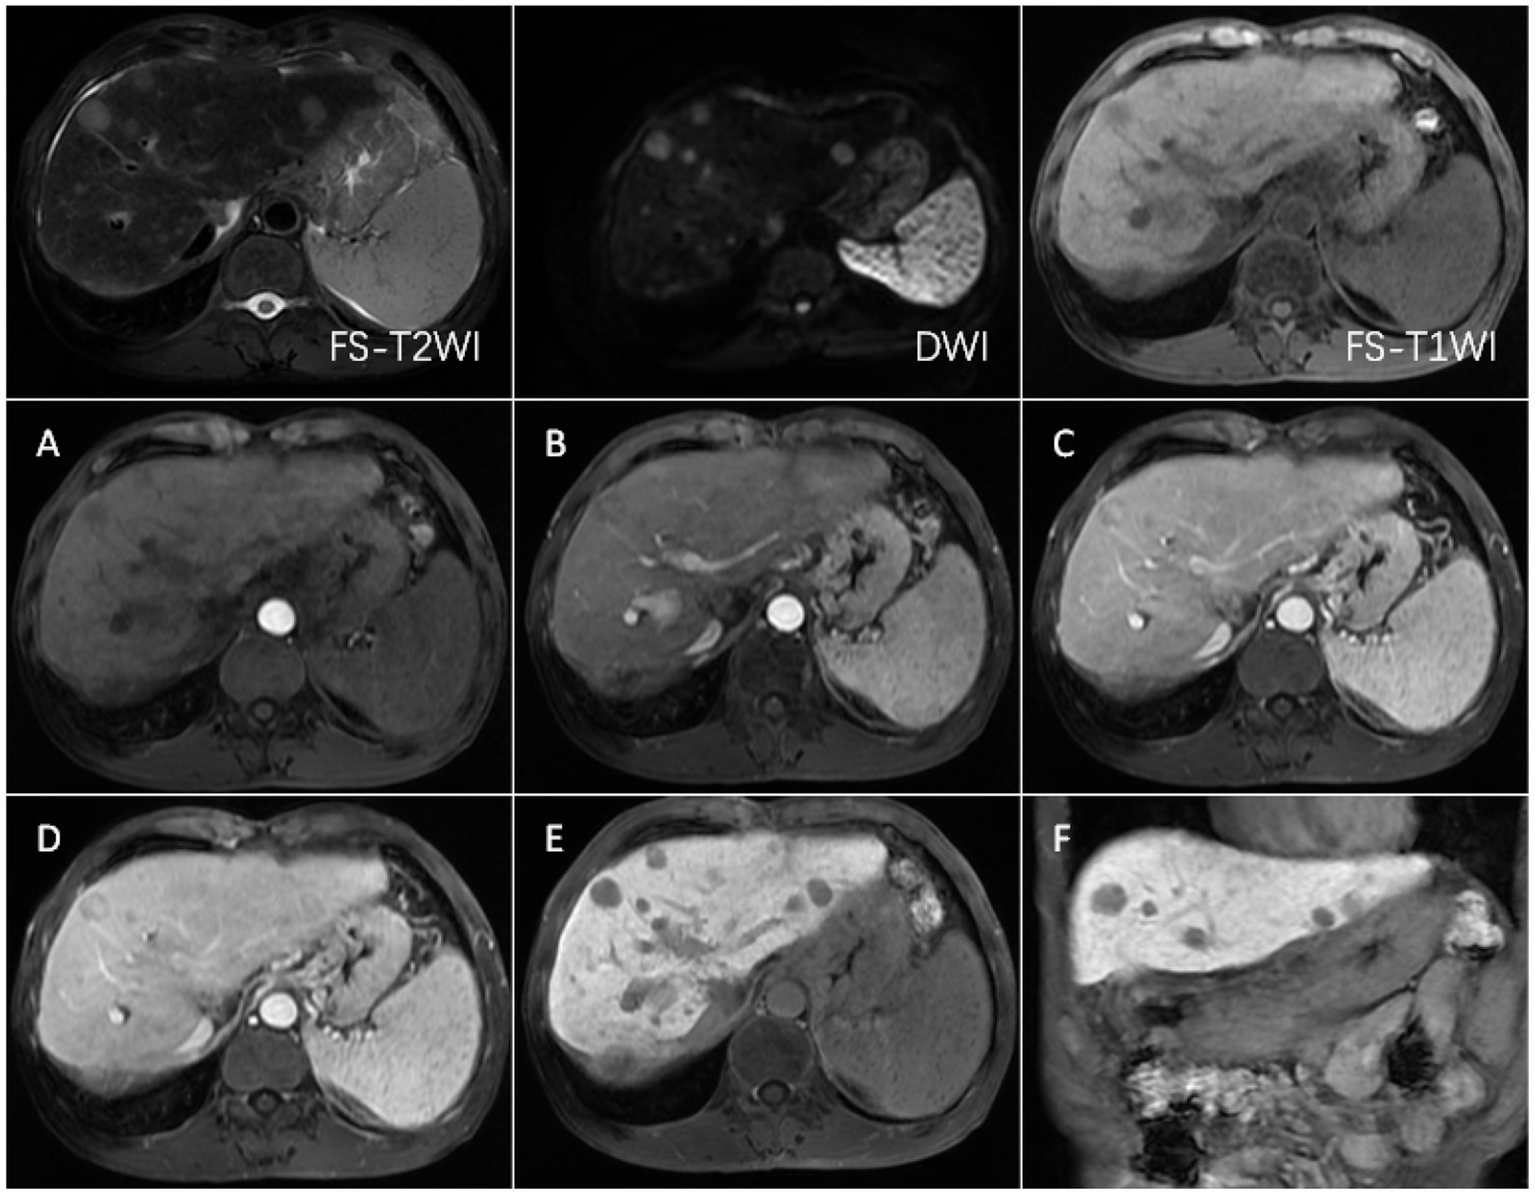

FS-T2WI and DWI: several round-like T2WI and DWI high-signal nodules were seen in the left and right lobes of the liver, with the largest being about 19.6 mm in diameter; FS-T1WI: several round-like low-signal nodules were seen in the left and right lobes of the liver. (A–F) show the early arterial, late arterial, portal venous, delayed, hepatobiliary axial and coronal positions. MRI dynamic scan: the lesion did not have definite enhancement in the early arterial stage, and it showed inhomogeneous and mild enhancement in the late arterial stage, with low-signal edges in the portal vein stage and the delayed stage, and high-signal in the central area; Hepatobiliary phase—axial and coronal: the lesion showed low signal, no contrast uptake was seen, suggesting that the multiple intrahepatic nodules were multiple HCC.

CECT scans were compromised by high-density lipiodol deposits, obscuring imaging clarity. In contrast, Gd-EOB-DTPA-enhanced MRI showed high signals during the arterial phase and low signals in the hepatobiliary phase for surviving and new lesions. The results of complete necrosis scans are shown in Figure 2 (Supplementary Figure 2); the results of partial survival scans are shown in Figure 3 (Supplementary Figure 3); and the results of new lesion scans are shown in Figures 4, 5.